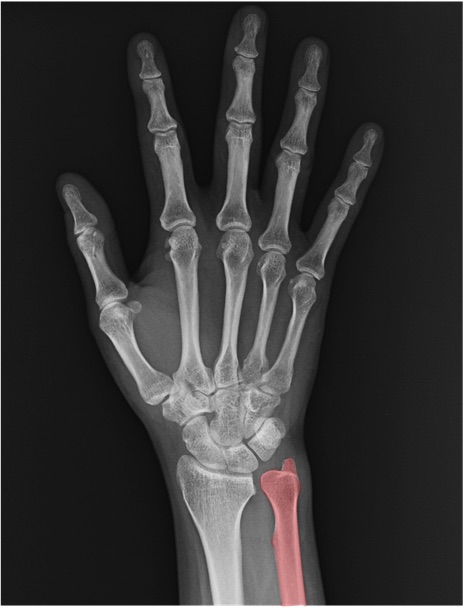

尺骨(ulna)の手関節レントゲン画像における正常解剖

橈骨(radius)

尺骨茎状突起(ulnar styloid process)

舟状骨(scaphoid)

月状骨(lunate)

三角骨(triquetrum)

中手骨(metacarpal bone)

基節骨(proximal phalanx)

中節骨(middle phalanx)

末節骨(distal phalanx)

CM関節(carpometacarpal joint)

IP関節(interphalangeal joint)

MP関節(metacarpophalangeal joint)

PIP関節(proximal interphalangeal joint)

DIP関節(distal interphalangeal joint)